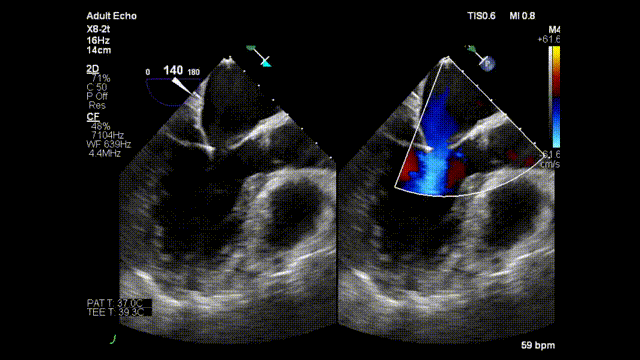

二尖瓣关闭不全动图

二尖瓣关闭不全动图,主动脉瓣关闭不全

二尖瓣关闭不全

二尖瓣关闭不全示意图

二尖瓣关闭不全超声